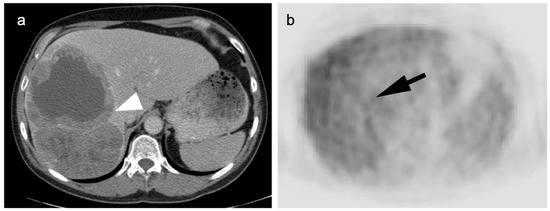

4. Hepatocellular Carcinoma